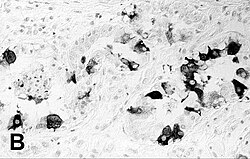

imunohistokemijsko bojenje pluća tuljana s PDV‑om | |